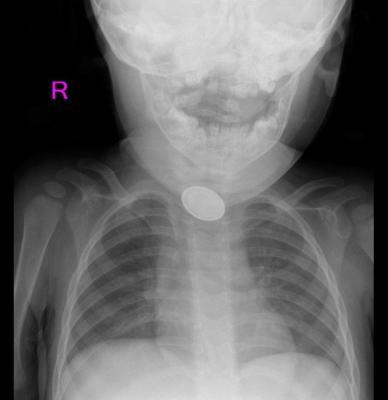

Kayseri'de 15 aylık A.Y.Ç.'nin yemek borusuna, evde oyun oynadığı sırada düğme pil ve lego oyuncak parçası kaçtı. O sırada yanında olan 4 yaşındaki kardeşi, 'Kardeşim lego yuttu' diyerek annesini çağırdı. A.Y.Ç.’nin ağızına bakan anne Tuğba Yılmaz, parçayı göremeyince dışkısından çıkacağını düşündü. Bir süre sonra A.Y.Ç.'nin yutma güçlüğü çektiğini gören Tuğba Yılmaz, Kayseri Şehir Hastanesi'ne başvurdu. A.Y.Ç.'ye yapılan röntgende, yemek borusunda düğme pil ve lego parçası oyuncağa rastlandı. Kız bebek A.Y.Ç., Kayseri Şehir Hastanesi Çocuk Cerrahisi ve Ürolojisi Anabilim Dalı Başkanı Doç. Dr. Mustafa Erman Dörterler ve ekibi tarafından ameliyata alındı. Yaklaşık 3 saatlik süren operasyonun ardından A.Y.Ç.'nin yemek borusuna kaçan düğme pil ile lego oyuncak parçası çıkarıldı.

Kayseri Şehir Hastanesi Çocuk Cerrahisi ve Ürolojisi Anabilim Dalı Başkanı Doç. Dr. Mustafa Erman Dörterler, "Hastamız 15 aylık bir bebek. Hastamız, disk pil ve beraberinde bir lego parçası yutmuş. Ben gece 01.30 gibi hastaneye geldim. Pili ve lego parçasını yutmasının üzerinden yaklaşık 6-7 saat geçmişti. Bu durumlarda dakika ve zaman çok önemli. 2 saatten sonra çok ciddi sıkıntılar oluşturabilecek hatta ölümle sonuçlanabilecek durumlarla karşı karşıya kalmaktayız. Ben, göğüs cerrahisi, çocuk gastroenteroloji, anestezi ekibi ve yardımcı sağlık personelleriyle beraber yaklaşık 20-25 kişiydik. Çocuğa, hızlı ve dikkatli bir şekilde müdahale ettik. Çünkü zaman ilerlediği için disk pil, yemek borusuna yapışmış ve delmek üzereydi. Dikkatli şekilde özenerek çıkarmaya çalıştık. Ekip çalışmasıyla beraber çıkarmayı başarabildik. Çocuğumuzun yoğun bakımdaki 2 günlük takip süreci devam ettikten sonra servisimize aldık. Şu an gayet iyi" diye konuştu.